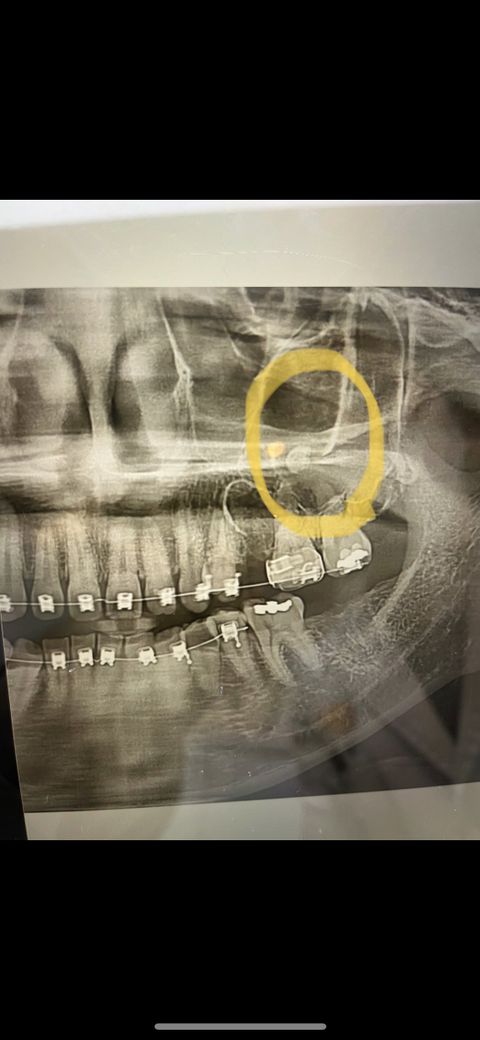

매복니 치아뿌리가 상악골? 로 올라가버렸어요

교정치과에서 교정을 위해 위에 매복니 치아를 부셔서

발치하단 도중 치아 일부 뿌리가 상악동? 쪽으로 올라가버려렸습니다 (코 옆근처)

많이 위험한 수술이 될까요 ? 걱정되서 사진첨부합니다

주황색 옆에 동그란 부분이 치아뿌리입니다